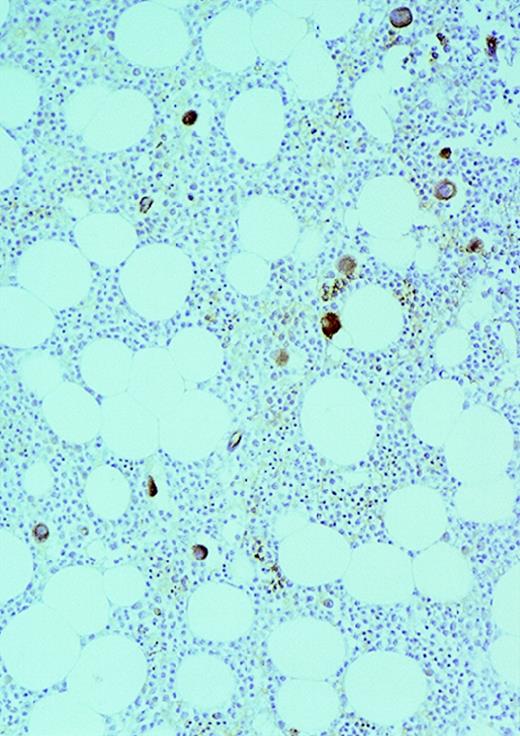

High-power view of vascularity of normal and AML marrow specimens.

Normal or AML bone marrow samples were stained for vWF expression (see Methods). A = 600× view of normal bone marrow showing positive staining in a megakaryocyte as well as 1 vessel. B = 400× view of representative AML marrow showing numerous vessels. Note that some of the vessels are large with irregular and bizarre shapes. C = 600× view of representative AML marrow showing details of vascular endothelial cell staining.